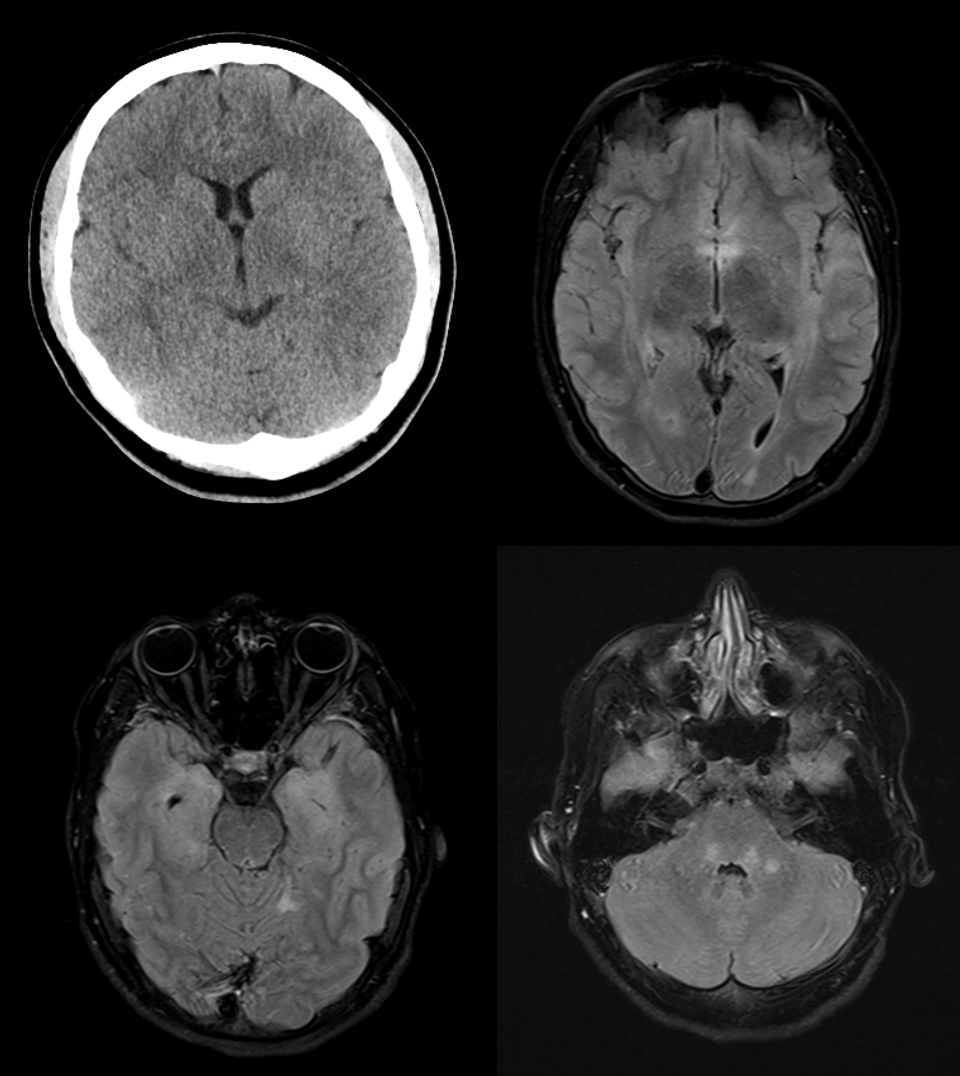

Mittels notfallmäßiger Computertomographie wurde eine Akutpathologie wie Blutung oder Infarkt ausgeschlossen. Anschließend wurde eine Magnetresonanztomographie durchgeführt, diese zeigte die folgenden pathologischen Veränderungen (siehe folgende Abbildung 1):

Die MRT-Untersuchung zeigte ausgeprägte T2w-Hyperintensitäten in der Medulla oblongata, weniger im kaudalen Tegmentum pontis, im zerebellären Marklager rechts, im subkortikalen Marklager am Hinterhorn links, insulär/temporal rechts, um die Temporalhörner, im posterioren Cingulum rechts und frontal beidseits. Der bildgebende Befund ist vereinbar mit einer limbischen Enzephalitis.